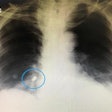

Imaging aids removal of aspirated dental crown